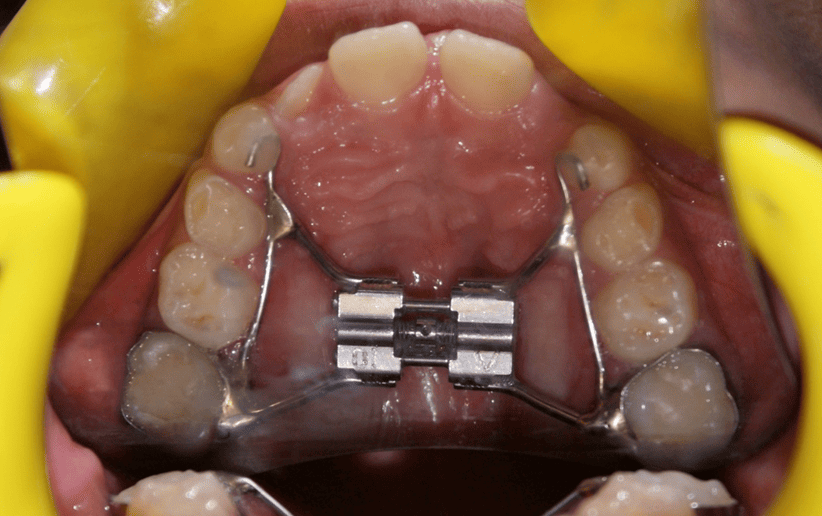

A palatal expander is a custom-made orthodontic appliance designed to gently widen the upper jaw (maxilla). This expansion helps create the necessary space for proper tooth alignment, corrects bite discrepancies such as crossbites, and improves overall jaw balance, airway function, and smile harmony.

• Appliance Placement: The expander is custom-fabricated and then bonded or cemented to selected upper teeth, typically the molars.

• Activation / Adjustment Phase: If using a screw-type expander, a small key is turned daily (or per protocol) to gradually widen the upper jaw. This gentle, steady force encourages new bone to form in the mid-palatal suture.